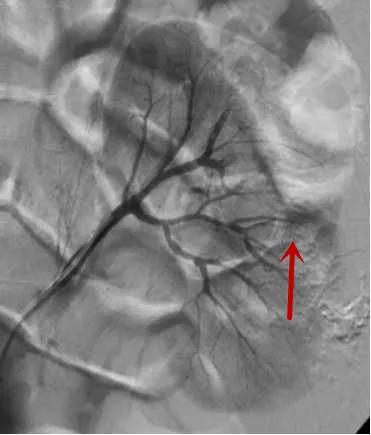

△造影找到出血动脉/找到出血责任动脉/精准栓塞后出血动脉已闭塞